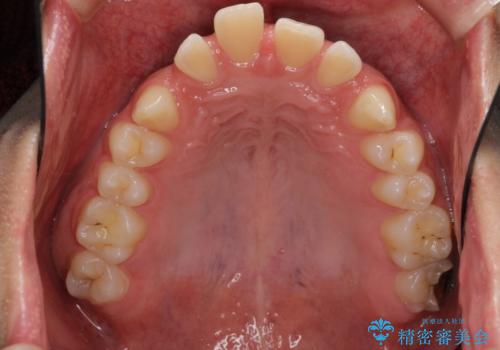

すきっ歯・出っ歯 コンプレックスの前歯を治したい 目立たない方法で セラミック治療は不可能な症例

- 前歯の並びを治したいと来院。

人前に立つ予定があるとのことで、初めはセラミックで歯を削ってかぶせる短期間で終える治療を希望されていました。

歯の位置が悪く、隙間も大きいためセラミックで被せても到底思ったような仕上がりにならないこと、下の歯が咬み込んでいるためセラミックはおろか前歯が短期間で折れてしまうリスクが非常に高いことを説明しました。

まだ20代と若く、これから歯をずっと使っていくことを踏まえて、前歯の角度や位置をしっかり変える矯正治療をおすすめしました。

上はインビザラインで目立たないように前歯を下げ、下は難しいため、ワイヤー矯正で咬み込んでいる下の歯を沈める処置を初め行いました。最終的には上下ともインビザライン矯正で仕上げました。